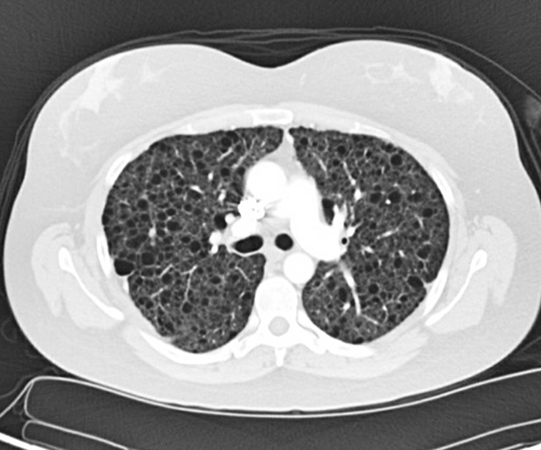

Clinical History: A 29-year-old female never-smoker with a history of a loculated left pneumothorax 2 years ago presented with a right-sided spontaneous pneumothorax prompting requirement for pigtail chest tube placement. A high-resolution computed tomography scan (HRCT) performed 3 months before the current presentation (Figure 1) showed innumerable bilateral subcentimeter thin-walled lung cysts.

Patients with LAM usually present with progressive dyspnea due to deterioration of pulmonary function, which may be worsened by exertion, as the disease process progresses. However, acute onset of dyspnea and chest pain in the setting of cystic lung disease warrants a suspicion of spontaneous pneumothorax due to LAM as in the current case. This is especially important in female patients of childbearing age, or under a clinical context of tuberous sclerosis syndrome with an obstructive or mixed obstructive and restrictive pattern on pulmonary function evaluation. Pleural effusion, hemoptysis, pulmonary hemorrhage, chylothorax and lymphadenopathies may also occur. The main radiological manifestation of LAM is the presence of multiple (>10), thin-walled, round, well-defined air-filled lung cysts of various sizes (2 to 40 mm in diameter) distributed evenly in both lungs.